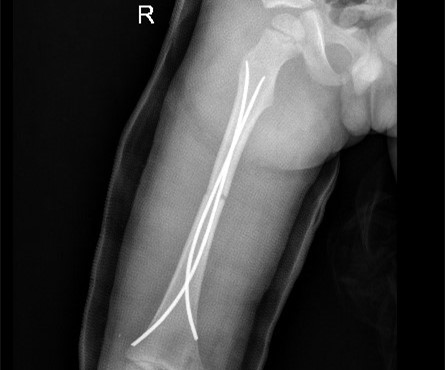

手术对皓皓的骨折部位进行了复位和内固定。

手术后,皓皓还要经过一段时间的康复治疗。

小儿骨科方科、李欣等医生为皓皓施行“右侧股骨干骨折切开复位内固定手术”。手术采用微创方式,使用弹性髓内钉固定,创伤很小,不会影响孩子的骨骼正常生长发育。术后,皓皓病情平稳,正在接受后续治疗。